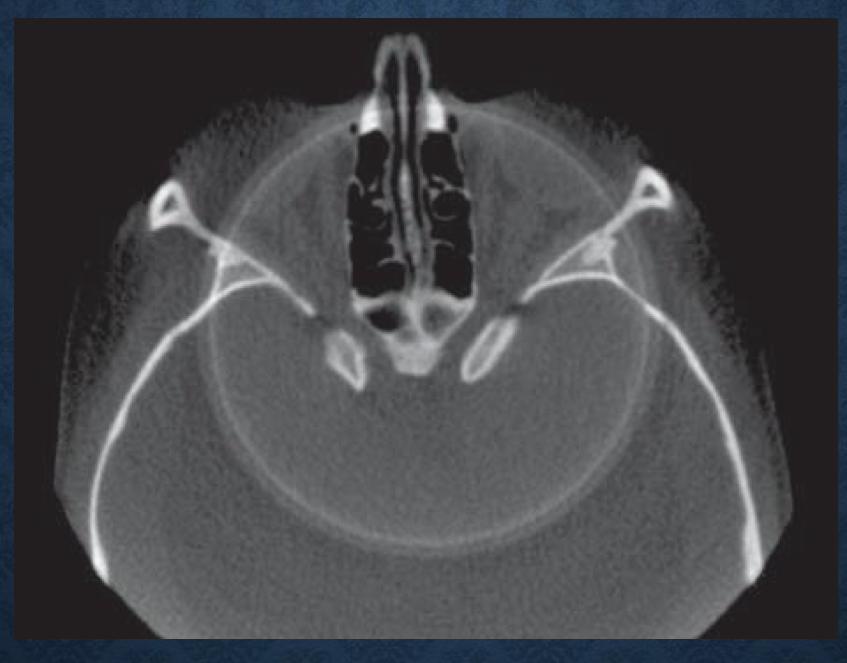

*what is this?

scanner related artifacts- circular rings on axial image indicating imperfections in scanner detection as a result of poor calibration